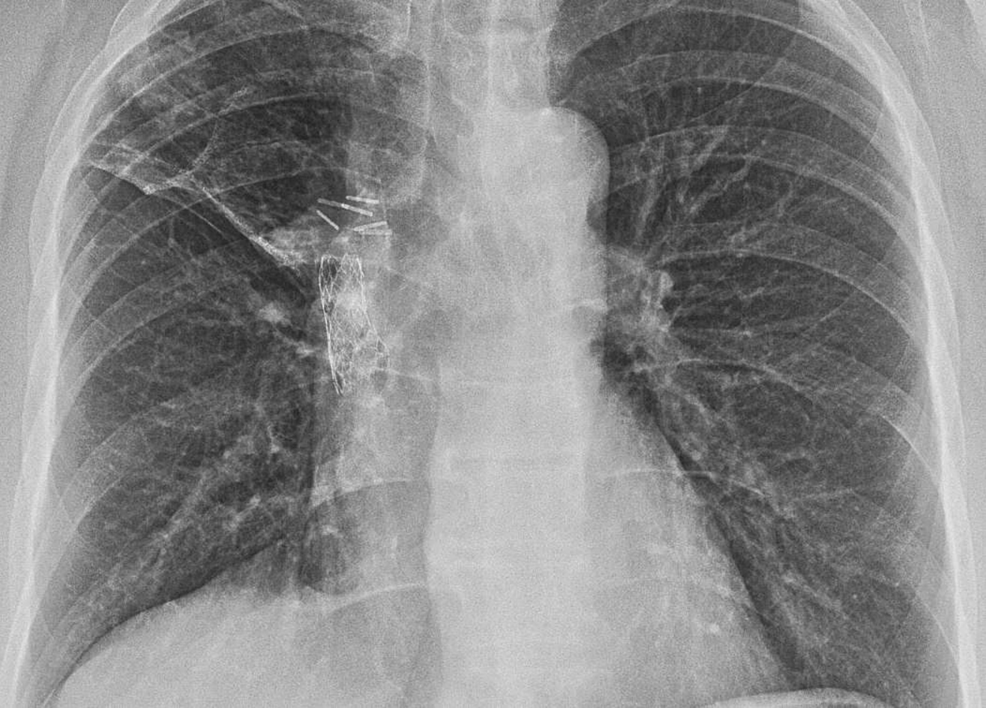

a Chest Xray with right sided pneumonia and effusion. b Chest Xray with

a Chest Xray with right sided pneumonia and effusion. b Chest Xray with Chest X-Ray Follow Up After Pneumonia The diagnosis of cap generally requires the demonstration of an opacity on chest imaging in a patient with a clinically compatible. Chest X-Ray Follow Up After Pneumonia.